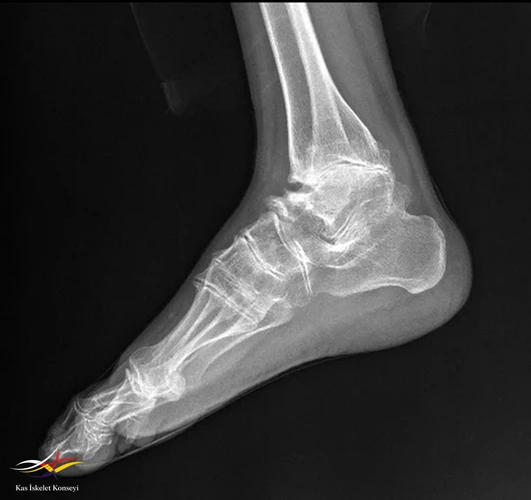

Resim 1.

Hikayesinden 5 yaşında coxa vara nedenli diz operasyonu (3 kez tekrar edilmiş), yaşını hatırlayamadığı bacak boyu uzatma operasyonu (çocukluk döneminde), 11 yaşında omuz cerrahisi (etyoloji aydınlatılamadı), 32 yaşında sağ kalça protez operasyonu öyküsü var.

Muayene: Fizik muayenede omuz, el bilek,dirsek, kalça, ayak bilek rom kısıtlı. El PIF'lerde şişlik, büyümüş kemiksi eklem görünümü? Boy kısa, kifotik görünüm mevcut? Artrit yok, ateş, kilo kaybı,oral aft genital ülser, ağız göz kuruluğu, Raynauld fenomeni yok.

2. Epifizyal değişiklikler: Uzun kemiklerin epifizlerinde irregular yapı, morfolojisi bozulmuş epifizler.

3. Ek bulgular: Omurga büyümesi normal doğumdan sonra başlar, ancak ergenlik öncesinde yavaşlar.